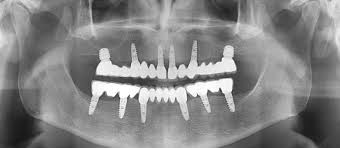

Implant restorations